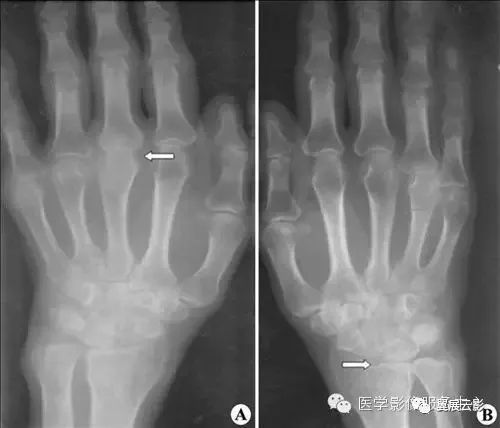

【普通放射图片】:

【影像表现】:X线正位片(A、B)示双手及腕诸骨骨质疏松,关节边缘破坏,关节间隙狭窄,桡骨关节面下骨质囊变(B,↑),近端指间关节软组织梭形肿胀(A,↑)。【影像诊断】:类风湿性关节炎(进展期)。